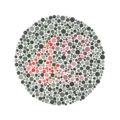

| •Colour vision: | to test colour vision |

| ••Ishihara's chart | to determine the type of colour blindness |

Ishihara Plate 9 Ishihara Plate 23

Ishihara Plate 23 A phoropter